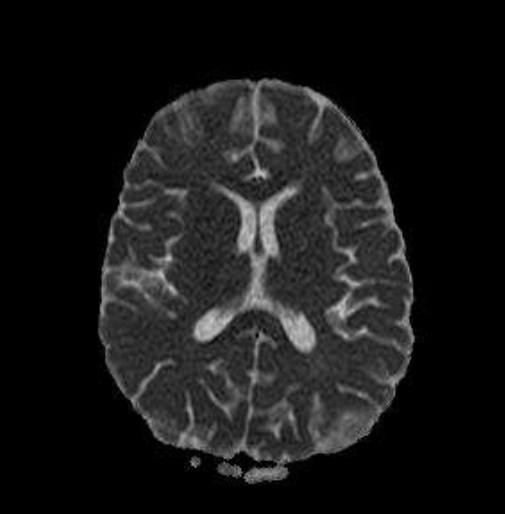

Alla RM encefalo si evidenzia una alterazione a margini sfumati senza enhacement a livello di nuclei dentati, porzione posteriore del ponte, nuclei subtalamici, talamo anteriore, teste dei nuclei caudati, ginocchio del corpo calloso, insule, della regione temporo-mesiale bilaterale, frontale, parietale posteriore e dei centri semiovali. I reperti coinvolgenti la sostanza bianca sottocorticale e i gangli della base in modo asimmetrico sono compatibili con riacutizzazione di processo infiammatorio (ADEM), per cui si imposta terapia con metilprednisolone (30 mg/kg in bolo) per 4 giorni seguito da prednisone per os con riduzione graduale in 4 settimane. La bambina presenta rapida risposta clinica e normalizzazione dell’EO e dell’EEG. Viene dimessa affidandola alla Neurologia per evidenziare una eventuale disseminazione spaziale-temporale delle lesioni, che sarebbe compatibile con una sclerosi multipla a esordio pediatrico.